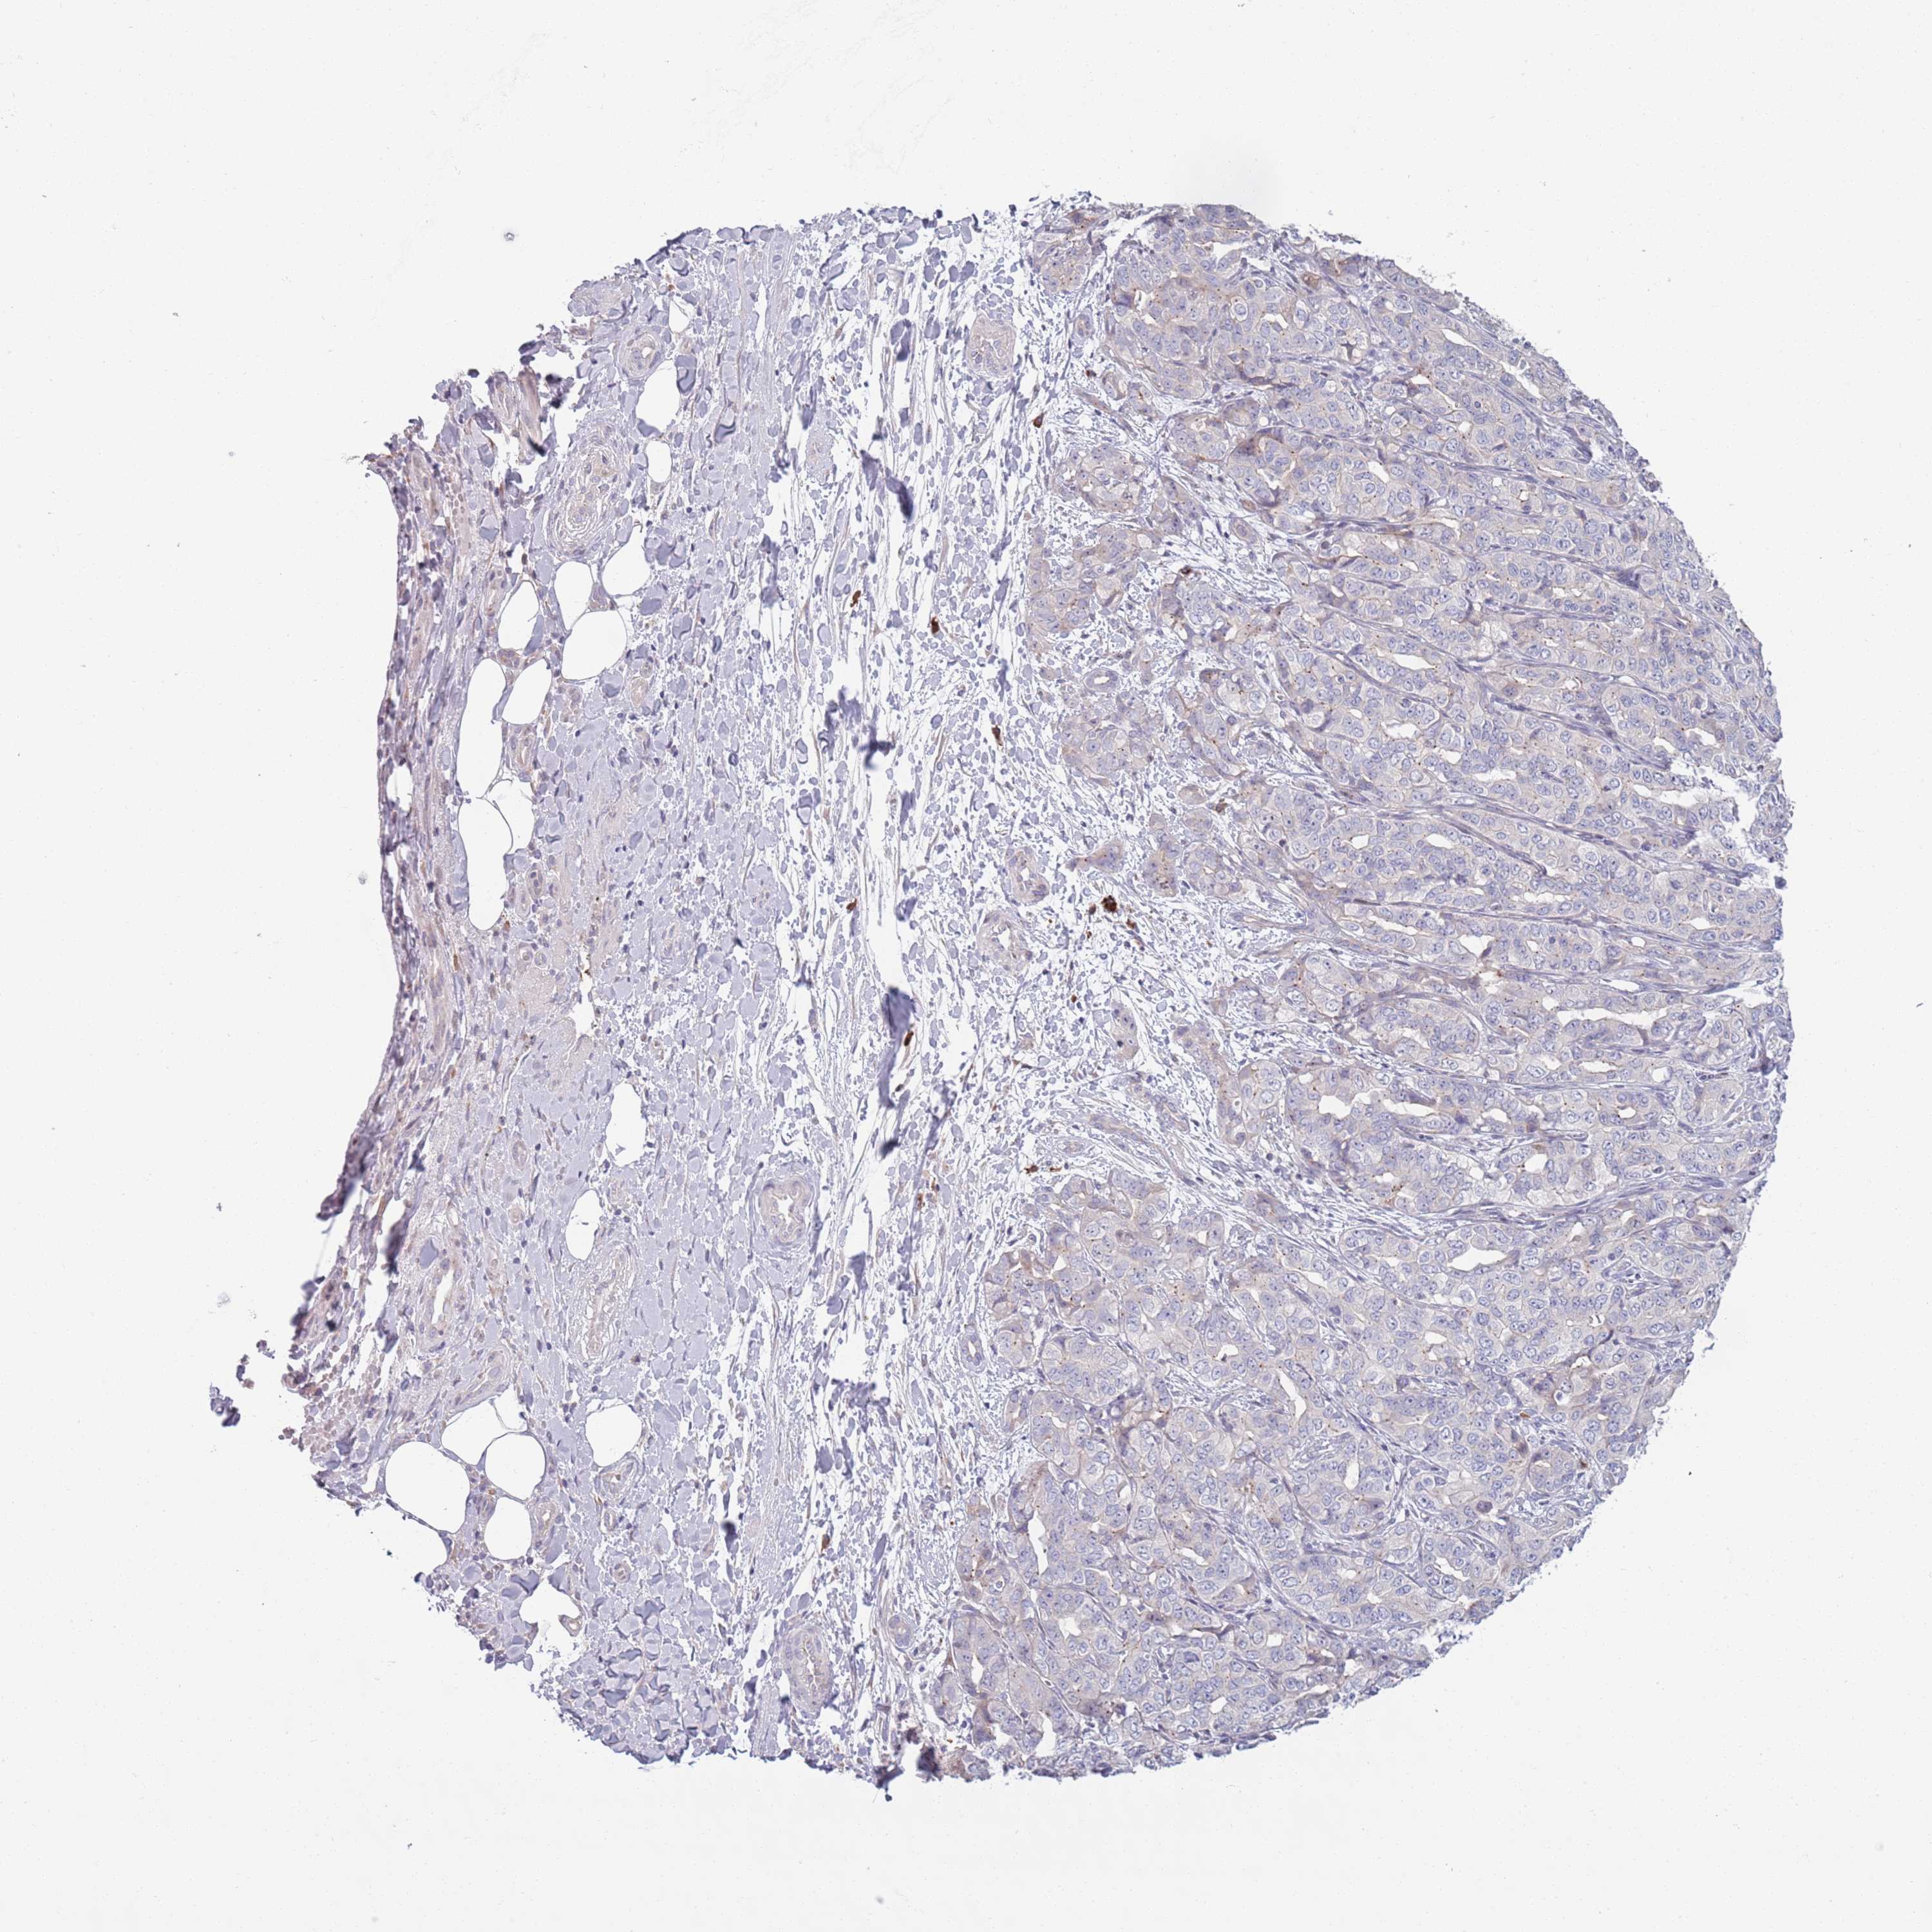

LIVER CANCER - Protein expressioni

A mouse-over function shows sample information and annotation data. Click on an image to view it in a full screen mode. Samples can be filtered based on level of antibody staining by selecting one or several of the following categories: high, medium, low and not detected. The assay and annotation is described here.

Note that samples used for immunohistochemistry by the Human Protein Atlas do not correspond to samples in the TCGA dataset.

Antibody stainingi

Antibody staining in the annotated cell types in the current human tissue is reported as not detected, low, medium, or high, based on conventional immunohistochemistry profiling in selected tissues. This score is based on the combination of the staining intensity and fraction of stained cells.

Each image is clickable and will lead to virtual microscopy that enables deeper exploration of all samples and also displays staining intensity scores, fraction scores and subcellular localization as well as patient and tissue information for each sample.

Antibody HPA048884

Staining

High

Medium

Low

Not detected

Intensity

Strong

Moderate

Weak

Negative

Quantity

>75%

75%-25%

<25%

None

Location

Nuclear

Cytoplasmic/membranous

Cytoplasmic/membranous,nuclear

Cholangiocarcinoma

Carcinoma, Hepatocellular, NOS